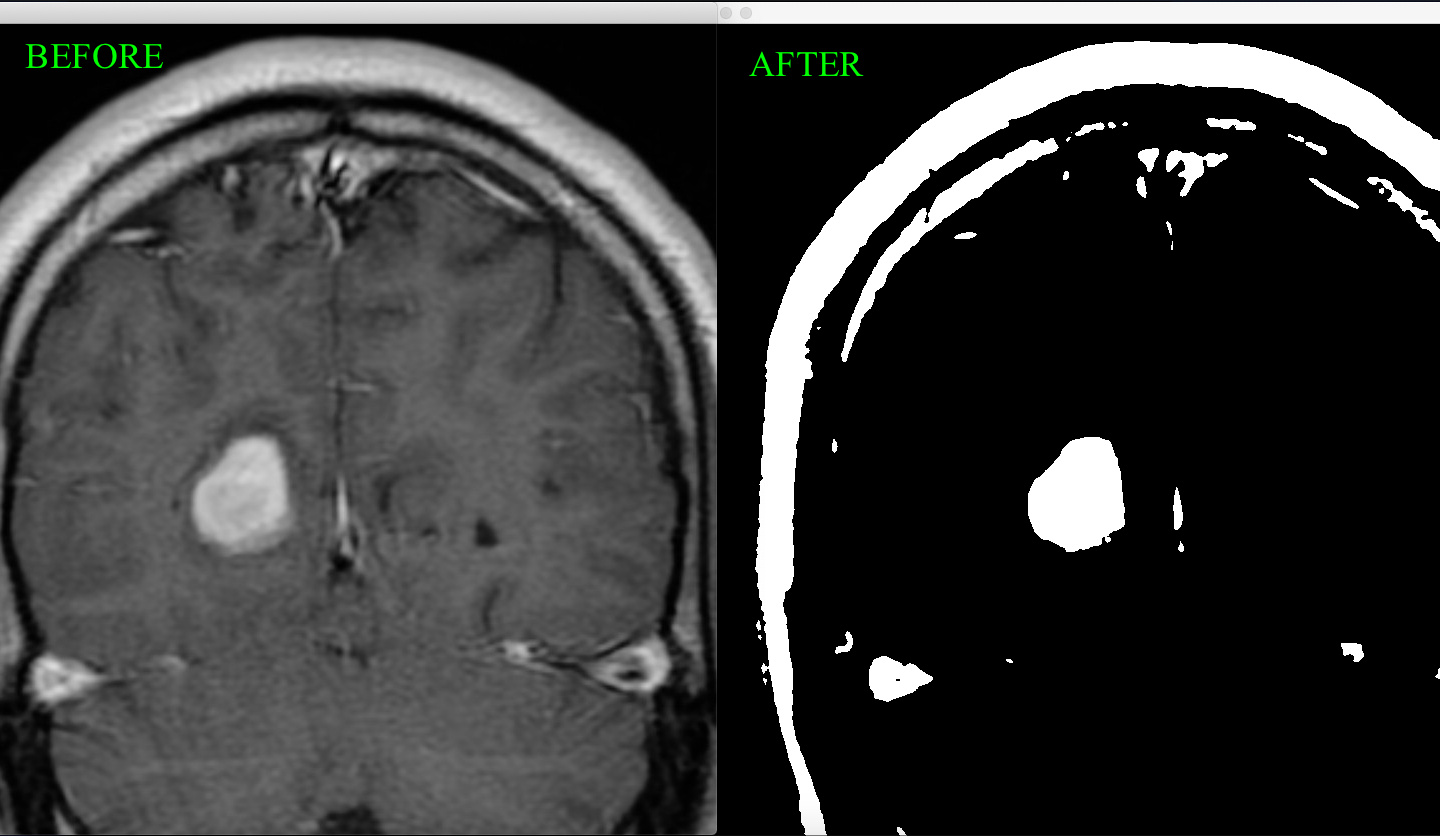

This tool takes in an image of an MRI scan, and uses various algorithms and functions to iterate through the pixels of the image and convert it to a cleaner, black and white image highlighting the specific area of the tumor. To write the code for this functionality, I had to code a grayscale filter to convert the image to grayscale, then code a median filter to reduce noise in the image, and lastly convert it to black and white. Another aspect I added was a function to determine if the tumor is a Meningioma, which means that it forms on the membranes that surround the brain. This function returns true or false depending on if the image is of a meningioma or not.

To create this tool, I had to do a lot of research. I looked at previous research papers and identified how images were manipulated to make an MRI scan clearer. I had to figure out an algorithm to identify the Meningioma. The functionality right now only checks for Meningioma on the left side of the brain. Essentially, a variable "measure" is set to 1/6 of the image's width, and since a Meningioma is attached to the membrane, the code checks for continuous white pixels within the "measure" unit to actually identify a Meningioma.